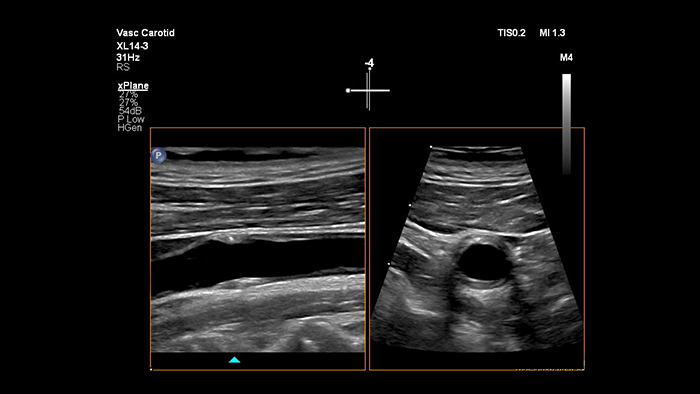

XL14-3 xMATRIXトランスジューサは、縦断面および横断面を同時にリアルタイムで描出して血管検査の標準アプローチを超える、xPlaneイメージングを提供します。xPlaneイメージングの主なメリットとして、トランスジューサを回転することなく直交断面を収集できる点が挙げられます。トラックボールのシンプルな動きで、完全な解剖学的評価を提供し、検査時間を短縮できます。

XL14-3 xMATRIXは、xPlaneドプラ機能も備えています。xPlaneパルスドプラは縦断面および横断面の参照画像を使用して、ドプラサンプルボリュームの位置決めを正確に行います。xPlaneドプラの主なメリットには、有意狭窄のサンプリング時に、サンプルボリュームの位置決めエラーを減少させ、高い再現性と一貫性を実現する点が挙げられます。